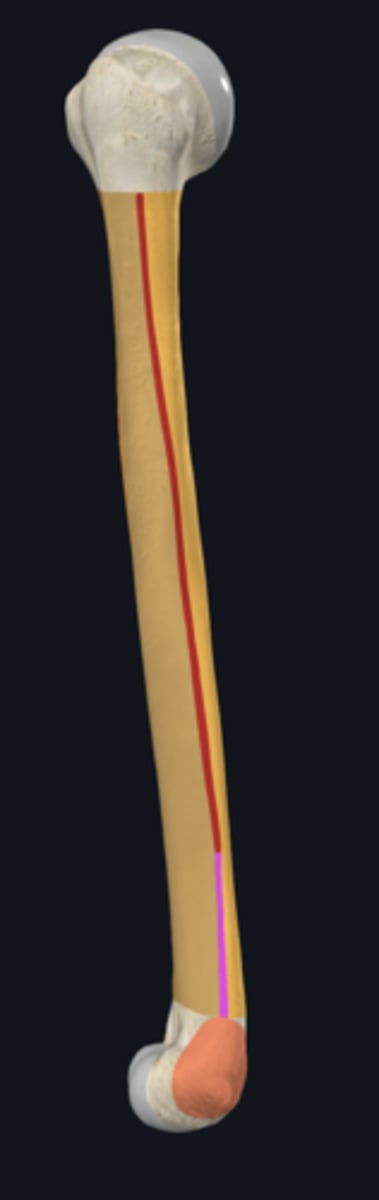

anatomical neck of humerus

body of humerus

condyle of humerus

anterior border of humerus

anterolateral surface of humerus

anteromedial surface of humerus

lateral border of humerus

medial border of humerus

posterior surface of humerus

deltoid tuberosity

radial groove

surgical neck of humerus